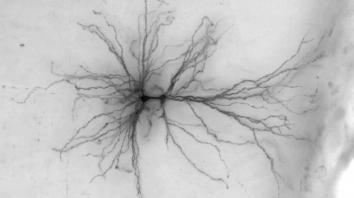

脑科学突破进展 计算机虚拟可活动人脑神经细胞模型

数世纪以来,科学家对大脑奥秘的了解仍然十分有限。艾伦脑科学研究所的科学家取得了突破性神经科学研究成果,通过大数据计算机创造出了活动的虚拟脑神经细胞模型,该研究能够使今后对人脑和器官的探究过程更加便利和深入。这项计算机模拟人脑神经细胞3D模型能够虚拟活体人脑细胞运作,其基于外科手术团...